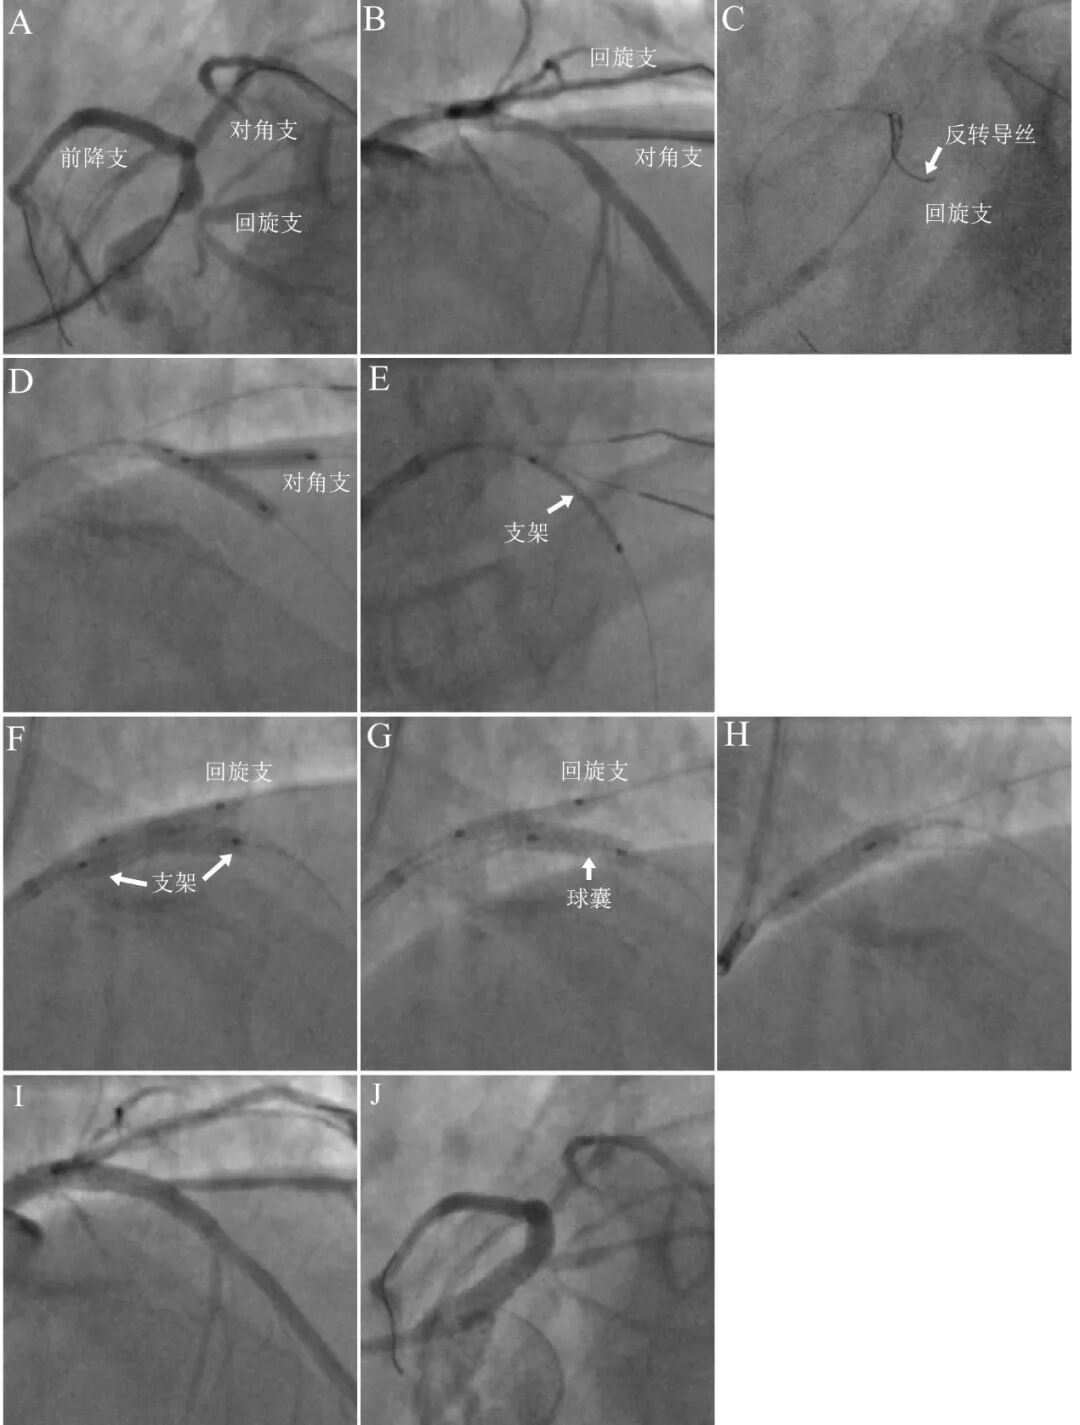

图4 球囊对吻预扩张和长程拘禁技术联合处理连续分叉病变。

真性前三叉病变,合并对角支开口分叉病变(A 蜘蛛位,B 右肩位)。介入策略分析:回旋支粗大,开口狭窄99%伴严重成角,属于重点保护分支;第一对角支开口狭窄70%,程度不重而且病变极端,因此闭塞可能性不大,属于次要保护分支。最初拟定方案是单支架方案:第一对角支采取球囊对吻预扩张,然后回旋支采用长程球囊拘禁技术,自左主干至前降支近端置入支架。介入准备工作顺利,采用反转导丝技术进入回旋支(C),前三叉病变球囊预扩张,对角支球囊对吻预扩张(D),但并未找到长度合适支架(该病例支架远端和左主干开口均需要精准定位,因此需要精确长度的支架),不得已最后采取双支架串联方案:对角支球囊对吻预扩张处理后,前降支近段置入3.018mm短支架(E,近端不超越回旋支开口);然后回旋支采用长程球囊拘禁技术,自前降支近端至左主干开口串联置入3.518mm短支架(F-H)。最后结果良好(I-J)。